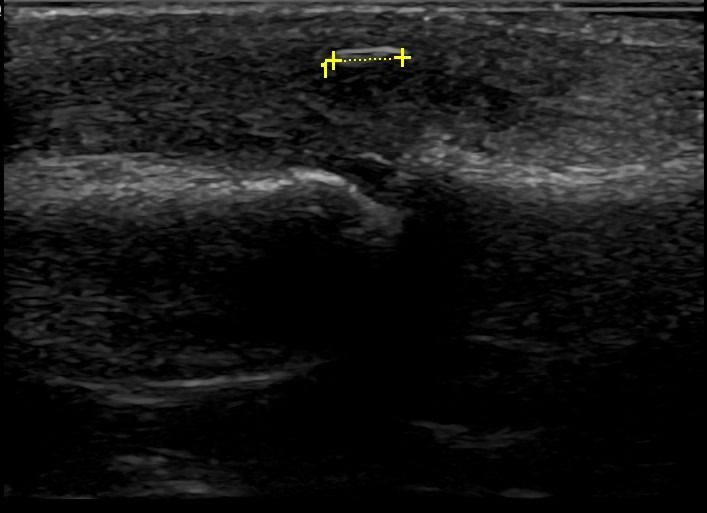

Peripheral Nerve Pathologies

- Nerve Entrapment Syndromes, such as Carpal Tunnel Syndrome

- Nerve Tumors

- Nerve Cross-Section